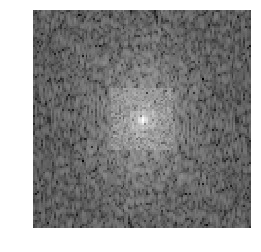

Medical image segmentation methods normally perform poorly when there is a domain shift between training and testing data. Unsupervised Domain Adaptation (UDA) addresses the domain shift problem by training the model using both labeled data from the source domain and unlabeled data from the target domain. Source-Free UDA (SFUDA) was recently proposed for UDA without requiring the source data during the adaptation, due to data privacy or data transmission issues, which normally adapts the pre-trained deep model in the testing stage. However, in real clinical scenarios of medical image segmentation, the trained model is normally frozen in the testing stage. In this paper, we propose Fourier Visual Prompting (FVP) for SFUDA of medical image segmentation. Inspired by prompting learning in natural language processing, FVP steers the frozen pre-trained model to perform well in the target domain by adding a visual prompt to the input target data. In FVP, the visual prompt is parameterized using only a small amount of low-frequency learnable parameters in the input frequency space, and is learned by minimizing the segmentation loss between the predicted segmentation of the prompted target image and reliable pseudo segmentation label of the target image under the frozen model. To our knowledge, FVP is the first work to apply visual prompts to SFUDA for medical image segmentation. The proposed FVP is validated using three public datasets, and experiments demonstrate that FVP yields better segmentation results, compared with various existing methods.